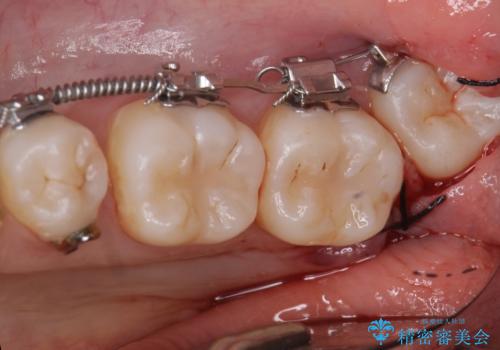

下の小臼歯を抜歯しましたが、その代わり下の親知らずを残して咬ませたので、歯の数は変わっていません。

ただし、左下の親知らずを残すには厚みのある歯ぐきを処置しています。(ディスタルウェッジ)

左上奥歯は、矯正後セラミックインレー修復を行なっています。

今回は左下の小臼歯を1本抜歯してるのと、手術を行なって親知らずを顎に収めることができました。